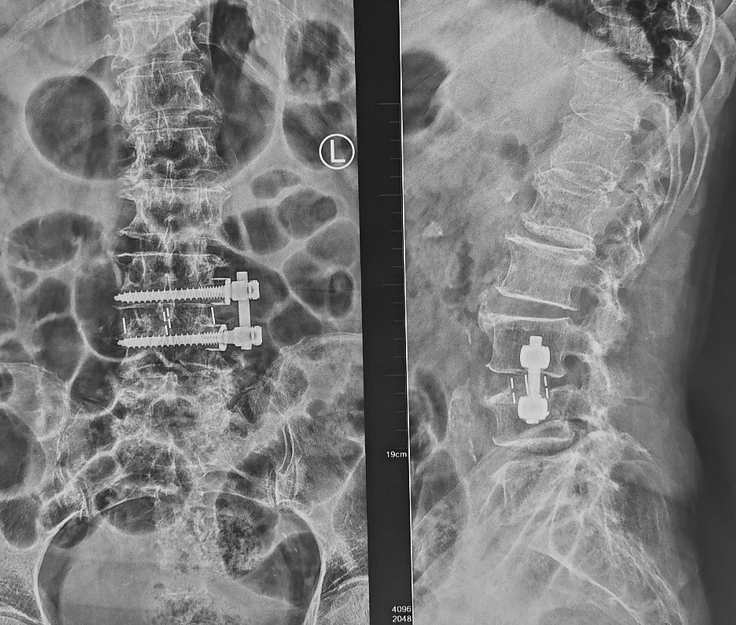

术后复查X线片

第一例患者女性,73岁,因“腰部反复疼痛20余年,加重伴左下肢疼痛4月”以“腰椎滑脱症(L3、 I°)、腰椎管狭窄症”住院。入院后经术前讨论、评估后制定治疗方案,并与患者及其家属充分沟通,行OLIF手术。术后第二天,患者下地活动,腰痛和左下肢疼痛完全消失,无明显不适,疗效满意。